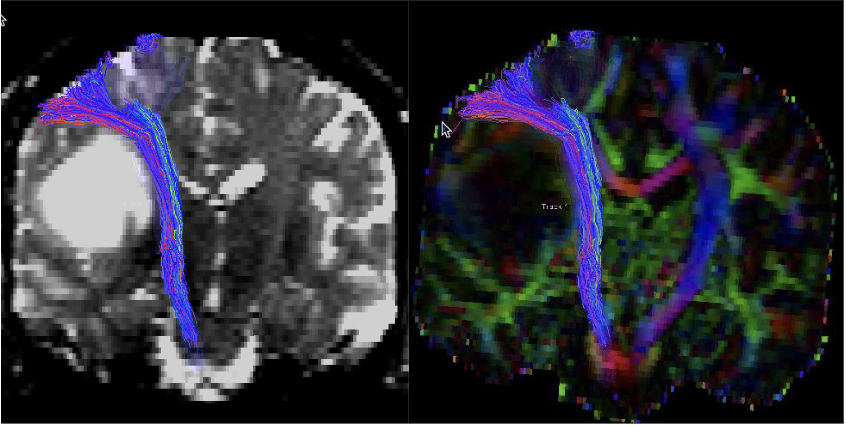

Vanitha Sankaranarayanan stood in awe, dressed head-to-toe in sterile scrubs, in the operating room. She observed as a neurosurgeon performed brain surgery guided by critical information from a diffusion tenser imaging (DTI) brain scan displayed on a digital screen. Through sensors on the patient’s physical brain, the surgeon could see the brain’s essential motor pathways colorfully illuminated on-screen, and where they were in relation to the tumor and how best to avoid them during surgery.

Observing this surgery shortly after she joined UCSF’s 3DLab in 2009 has influenced her work ever since. This experience gave her an opportunity to see how DTI tractography – the eloquent neuronal pathways she was hired to create through post-processing of MRI images – were being used in a neurosurgical procedure.

In the beginning, Sankaranarayanan’s work focused on interior brain tractography of motor pathways. Then neurosurgeons requested to see optic and language pathways too, which Sankaranarayanan now includes, using the same DTI techniques that involve seeding a region of interest on the MRI, and then working with an algorithm to generate the pathways. Advances in technology and computing power have dramatically reduced the processing time for brain tractography, increasingly used when tumors are located close to motor, optic, and language pathways. Now, DTI imaging is also being used for arteriovenous malformation (AVM) and epilepsy pre-op cases.